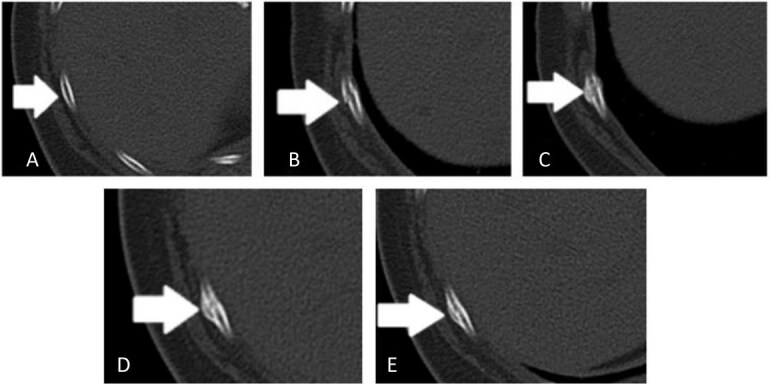

Trauma in victims of abuse often exists in various ways, and the characters usually manifest as non-fatal injuries, repetitive occurrence, and the injured parts are relatively hidden. Forensic experts are optimally positioned to raise suspicion for abuse when comprehensively considering a forensic investigation, reviewing imaging, and other multiple factors of geriatric injury victims. However, few experts received formal or informal training in abuse identification. In this article, we discussed two cases of suspected victims of abuse with rib fractures and attempted to determine the location, timing, and directionality of these injuries to raise the index of suspicion for abuse. We present two cases to characterize the radiographic changes of rib fractures in various stages of healing and radiographic findings in elder abuse events. To improve the accuracy of the imaging diagnosis, we collected a series of computed tomography images of rib fractures and compared all computed tomography images of these two victims with these images. We found that the victims presented with repeated rib fractures and with different stages of healing. We strongly suspect these were abuse cases due to the radiographic findings and clinical recordings demonstrated by these cases. We aim to raise awareness of abuse in radiology and forensic medicine to help these victims and reduce such incidents.